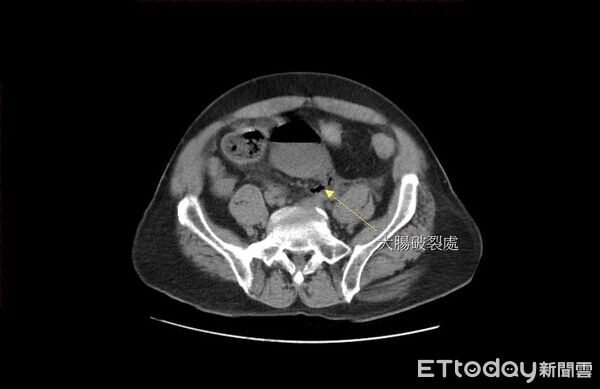

▲苗栗65歲老翁自行灌腸,不慎造成腸破裂、糞水亂流引發腹膜炎,送醫手術後救回一命。(圖/大千綜合醫院提供,下同)

苗栗縣65歲黃姓老翁,長期飽受便秘所苦,每天都服用強力軟便劑,甚至每隔2~3天就自行灌腸,日前甚至改用更長的管子,把瀉藥送入直腸深處灌腸,沒想到竟突然引發劇痛,緊急送至大千綜合醫院急診,經電腦斷層掃描後赫然發現,在直腸上端處有一個巨大的破洞,糞水隨著破洞流進腹腔,引發嚴重的腹膜炎,幸好緊急手術救回一命。

馮啟彥緊急進行腹腔鏡手術,術中發現直腸上端靠近乙狀結腸的轉彎處,有一個直徑2公分的破洞,研判應是太用力灌腸造成的腸道破裂,也讓大量的宿便流進腹腔,才會引發嚴重的腹膜炎。所幸,病人在接受手術後順利康復,也嚇得直呼「再也不敢自己隨意灌腸了!」